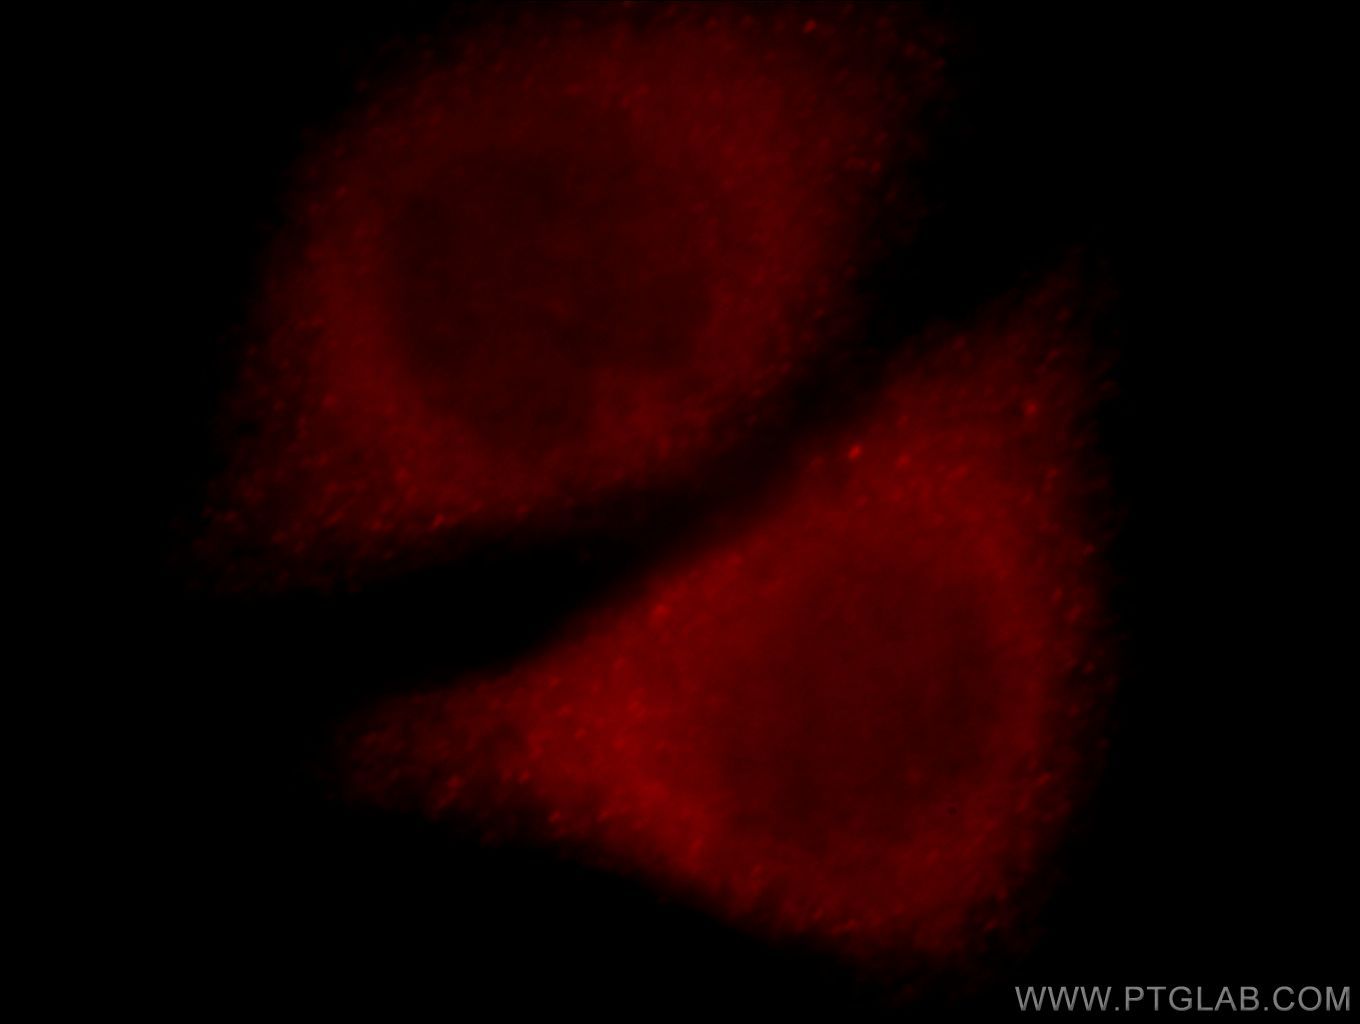

Supportive validation

- Submitted by

- Proteintech Group (provider)

- Main image

- Experimental details

- Immunofluorescent analysis of Hela cells, using SLC10A3 antibody 19909-1-AP at 1:25 dilution and Rhodamine-labeled goat anti-rabbit IgG (red).

- Sample type

- cell line